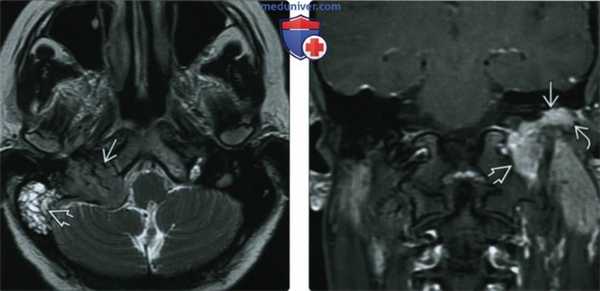

(Слева) При аксиальной МРТ Т1 ВИ С+ FS правой височной кости определяется контрастирующаяся ГТП, заполняющая среднее ухо. Обратите внимание на гипоинтенсивные слуховые косточки, погруженные в опухоль. Определяется обструкция входа в пещеру, приводящая к появлению неконтрастирующейся жидкости в ячейках сосцевидного отростка.

(Справа) При аксиальной MPT Т2 FS в среднем ухе определяется гломусная опухоль с промежуточной интенсивностью сигнала по сравнению с гиперинтенсивным содержимым в сосцевидном отростке. Обратите внимание, что задний край опухоли приводит к обструкции входа в пещеру.

(Слева) При корональной КТ в коаном окне визуализируется маленькая ГТП, расположенная в нижних отделах мыса улитки, сразу же краниальнее и медиальнее барабанного кольца. На единавенном корональном изображении ГТП выглядит практически неотличимой от аберрантной внутренней сонной артерии (ВСА), однако в этом случае ниже улитки видна нормальная ВСА.

(Справа) При корональной МРТ Т1 ВИ С+ FS определяется ГТП в виде едва заметного фокуса накопления контраста снизу и снаружи от улитки. Без данных анамнеза рентгенолог легко может пропустить такую маленькую ГТП.